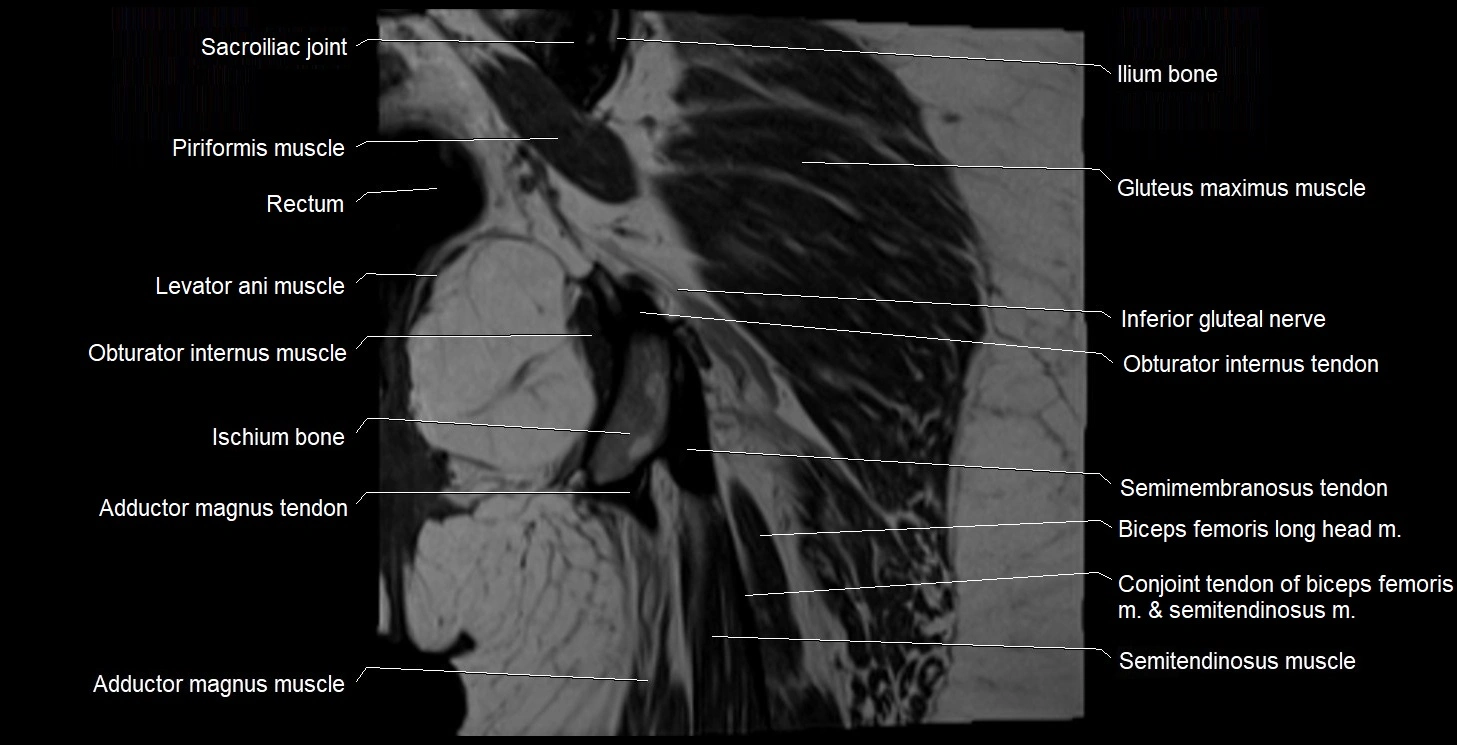

- Adductor magnus muscle

- Conjoint tendon of biceps femoris & semitendinosus

- Gluteus maximus muscle

- Ilium bone

- Ischial tuberosity

- Ischium bone

- Levator ani muscle

- Obturator internus muscle

- Obturator internus tendon

- Rectum

- Sacroiliac joint

- Semimembranosus tendon (proximal)